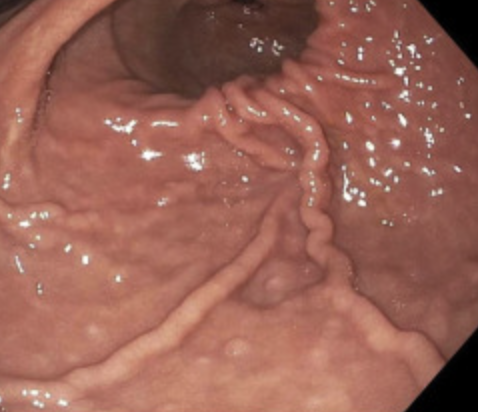

Enhanced Suction During Esophagogastroduodenoscopy: Official journal of the American College of Gastroenterology | ACG @AmCollegeGastro Congratulations @ZSobaniMD and @swathipaleti for putting this idea into video @AmJGastro #ThinkingOutsideTheBox #endoscopy #innovation